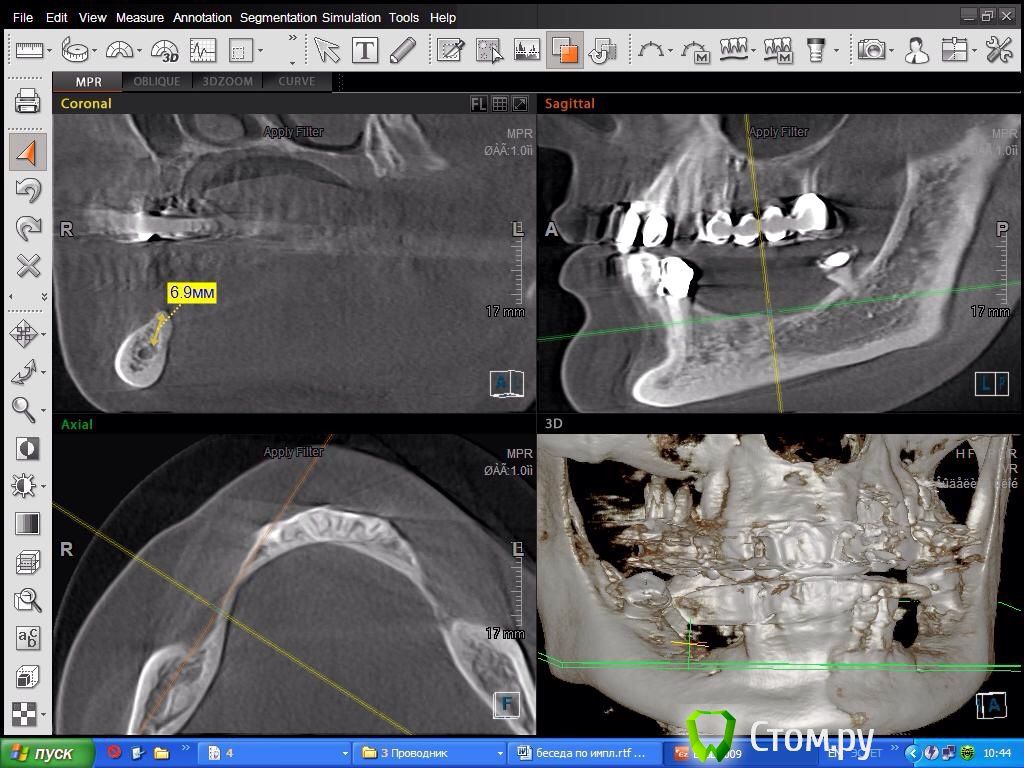

SDC Опубликовано 8 октября, 2014 Поделиться Опубликовано 8 октября, 2014 Склоняюсь в 4 кв делать консоль! Спасибо за мнениеПосмотрим срезы на уровне 2 премоляра? Получится ли имплантировать в этом месте? Ссылка на комментарий

DoktorDre Опубликовано 8 октября, 2014 Автор Поделиться Опубликовано 8 октября, 2014 Посмотрим срезы на уровне 2 премоляра? Получится ли имплантировать в этом месте?Получится, после ламинатов) Ссылка на комментарий